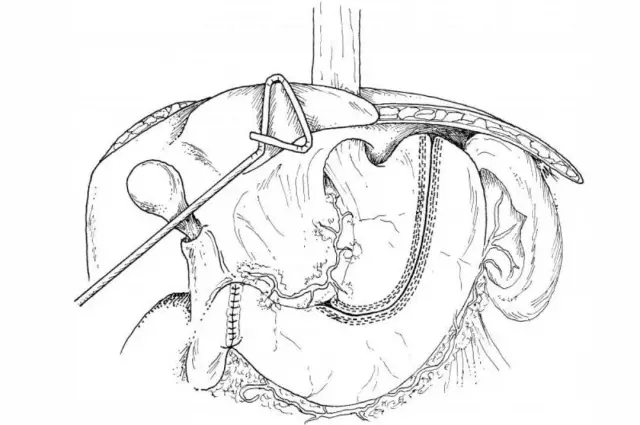

剪胃制作管状胃

来自Internet图片搜索

.根据临床资料和多年的临床经验,胡迪主任发现,不同部位胃壁组织厚度不同,一般遵循这样的规律,从胃底经胃体到胃窦,胃壁组织依次增厚,为了达到良好的缝合和止血目的,不同部位需要采用不同型号的切割吻合器钉仓,这样才能保证缝钉成型高度符合组织缝合厚度的需要。

.如果从胃底开始裁剪,胡迪主任第一次击发选用蓝钉仓,第二次击发选用金色钉仓,第三次击发选用绿色钉仓,直到结束。第一次和第二次击发的长度,需要根据实际管壁厚度的变化,来调整有效的切割长度。

胡迪主任发现,市面上能够流畅击发,达到良好缝合止血效果的切割吻合器产品不多。健瑞宝医疗能充分考虑胸外科医生的临床需要,为临床提供55毫米蓝色、黄色和绿色钉仓,这样制作管型胃就游刃有余。有的企业尽管提供75毫米蓝色、黄色和绿色钉仓,但是与55相比,依旧欠灵活。